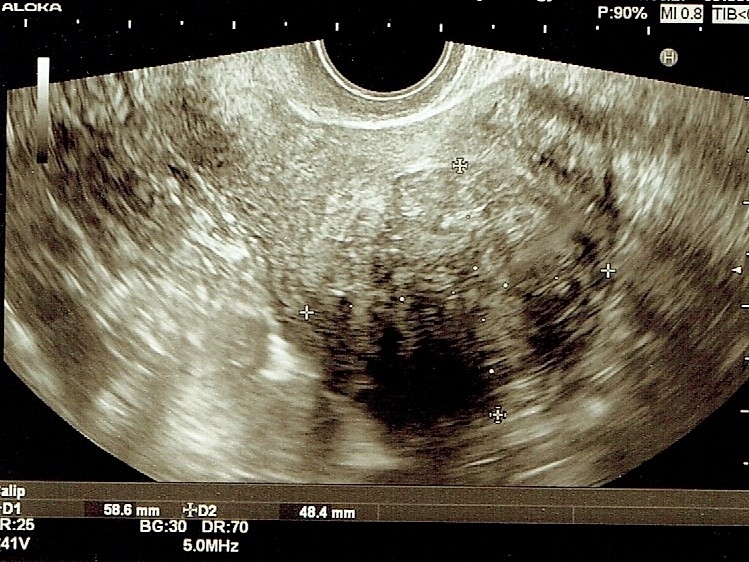

超音波検査上、筋腫は徐々に増大し、最大59×48mmで、子宮内腔にも30~40%突出してきていました。

ナファレリールを3ヶ月使用し、45×40mmと筋腫がわずかに縮小したところで、1回目手術を施行しました。

1回目手術時間約30分、子宮腔内に突出部分は切除しましたが、術後の残存筋腫は37×28mmでした。